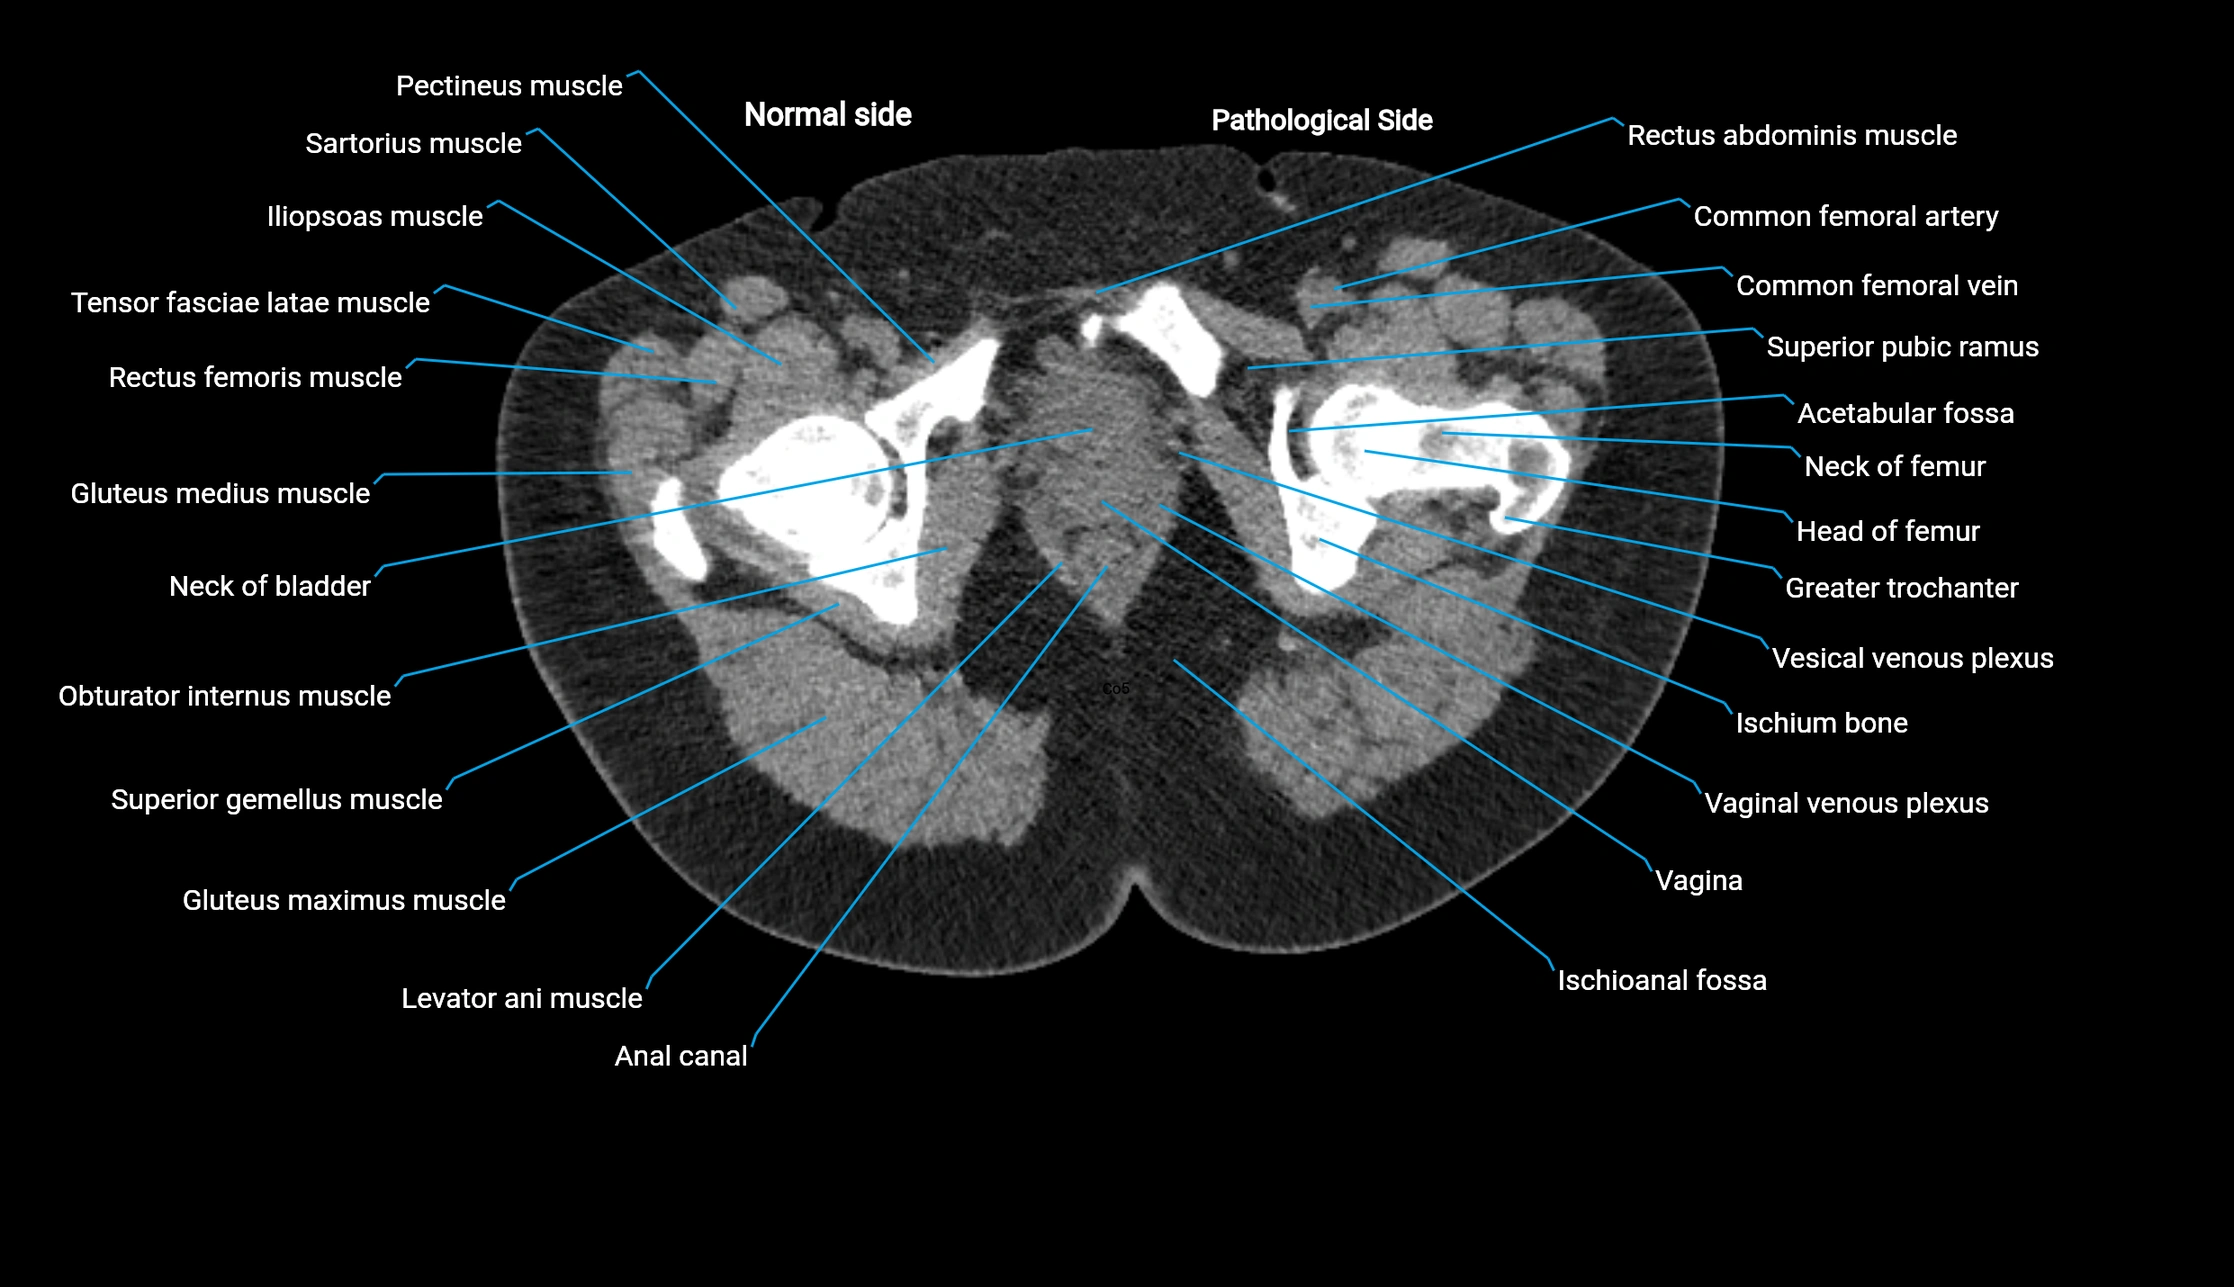

CT image

image